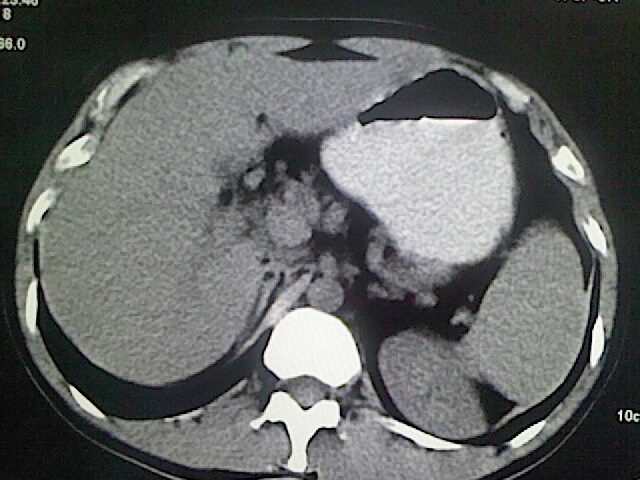

以下是引用卜一在2009-3-14 9:49:00的发言:[br]胆囊萎缩,胆囊壁不规则增厚,内部结构模糊,增强明显强化。另:肝左叶外侧段肝囊肿。支持:慢性胆囊炎!高度可疑:胆囊癌!

以下是引用余辉在2009-3-14 8:48:00的发言:[br]1)慢性胆囊炎。2)肝左叶外侧段肝囊肿。3)脂肪肝。[br]支持,胆囊萎缩,密度增高,不知b超具体有何提示,钙胆汁?结石?

以下是引用jiangjing在2009-3-14 10:18:00的发言:[br]1)慢性胆囊炎。2)肝左叶外侧段肝囊肿。3)脂肪肝。4.】建议行肝功能检查